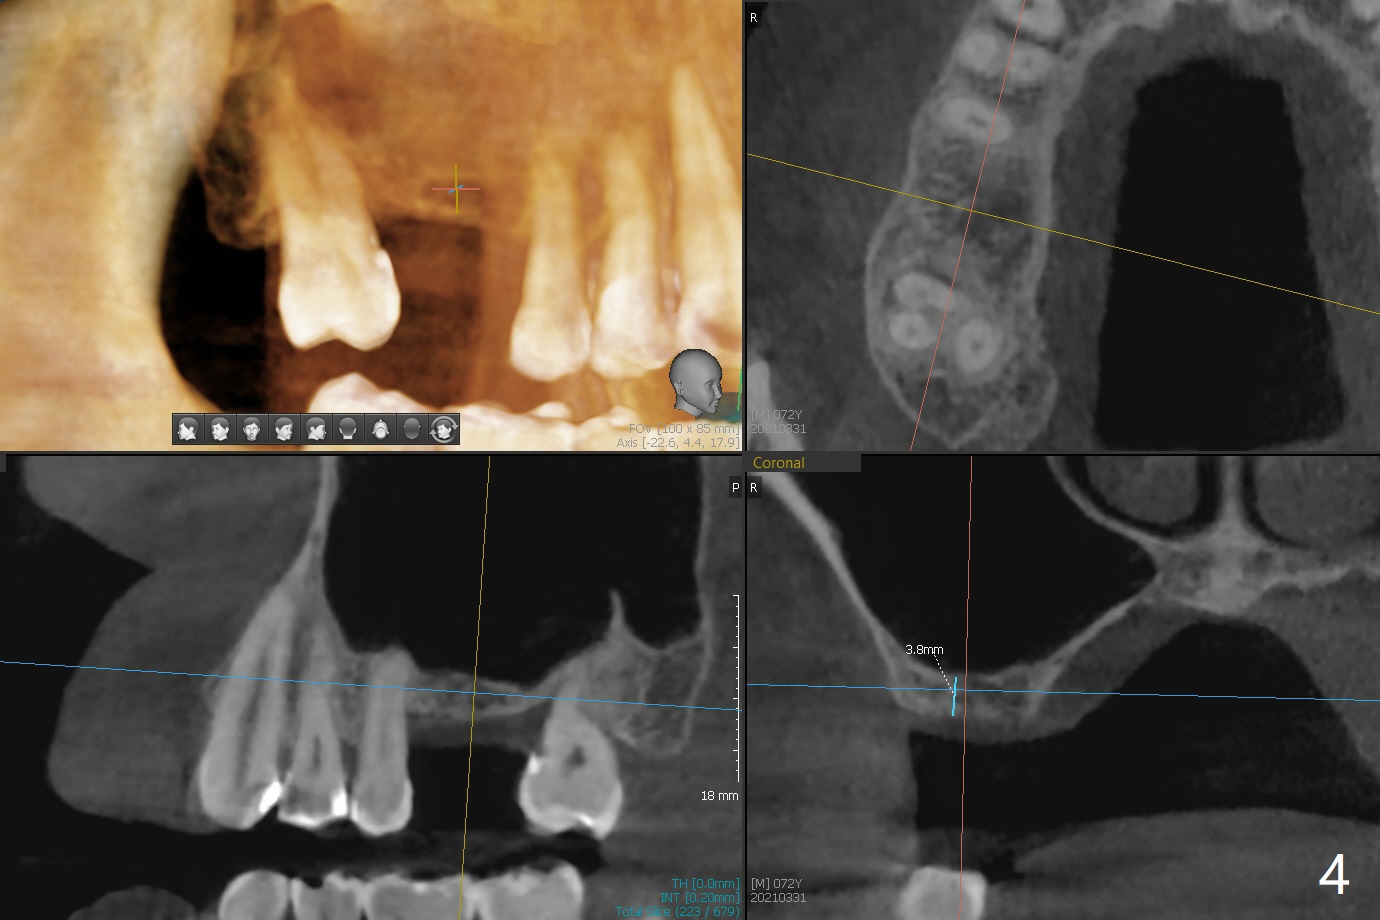

A 72-year-old man agrees to have #14 to be extracted for implant (Fig.1). In the first stage, impression is taken for #14 and 18 implant placement with guide. Due to odontogenic sinus infection (Fig.1,2 *), Z pack will be taken to prevent implant infection associated with sinus lift (Fig.2). Remove provisional and abutment once the sockets heal. To combat #15 supraeruption, the implant at #18 will be placed deep; if the torque is high, place a large diameter healing abutment or provisional with large base will be fabricated so that a short cuffed abutment will be used for final restoration. Heavy occlusal reduction at #15 will be conducted (Fig.3 curved lines). In spite of the fact that the bone height at #3 is 3-4 mm, the sinus floor is flat (Fig.4). Internal sinus lift is not expected to be too difficult. Use Magic Sinus Lifter, followed by implant placement at the same stage (Fig.5,6).